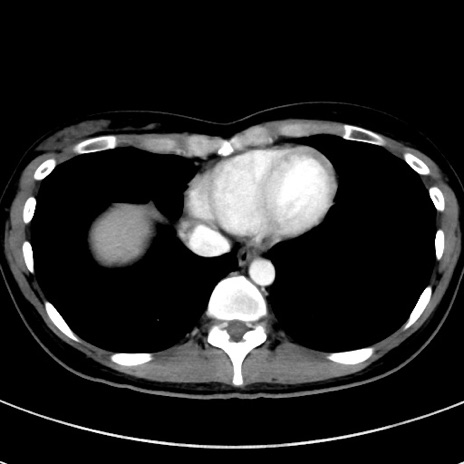

症例17(横断像)

【症例】20歳代女性

【主訴】嘔吐、下腹部痛

【現病歴】昨日夕食後に嘔吐し下腹部痛が出現。本日になっても嘔吐持続し改善しないため来院。

【身体所見】意識清明、BT 37.2℃、BP 108/67mmHg、腹部:平坦、やや硬、下腹部正中から右にかけて圧痛あり、反跳痛軽度あり、tapping pain(+)。

【データ】WBC 13600、CRP 14.94